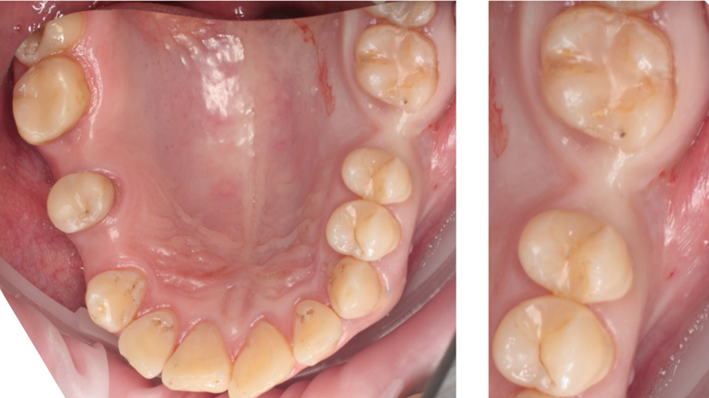

Clinical case: # 46 implant placement & GBR using i-Gen membrane for significant vertical resorption & mixed bone defect

AnyRidge, mandibular posterior, i-Gen, resorption, bone defect, bone regeneration, space management, #46, GBR, Dr. Iulian Filipov

“AnyRidge KnifeThread achieves excellent stability in regenerated bone & even in only 3mm bone height!”